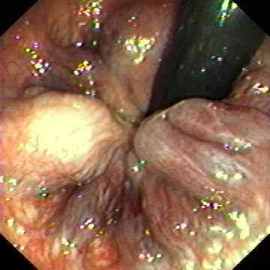

Anus:Internal hemorrhoids seen with the endoscope in an inverted position